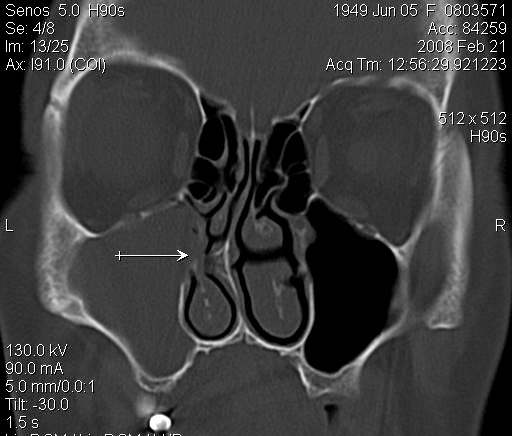

JFC Aticitis colesteatomatosa.

JFC Etmoiditis bilateral

JFC Sinusitis maxilar. Espolón septal.

JFC Sinusitis Maxilar